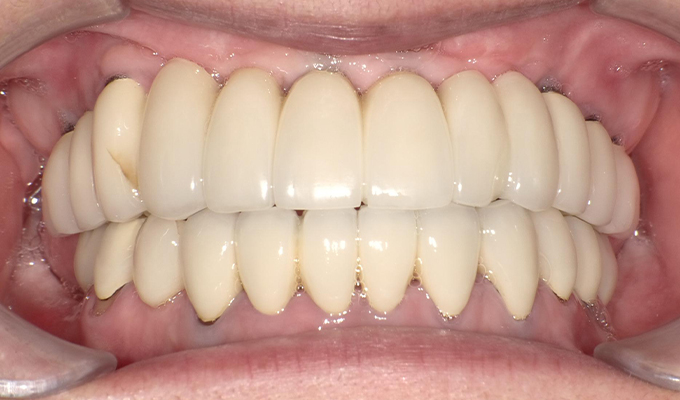

case3インプラントとハイブリットセラミックスの症例

初診時(2012年)

初回メンテナンス時(2014年)

最新メンテナンス時(2024年)

- 初診時の年齢

- 50代男性(2012年)

- 主訴

- 左上の前歯が欠けた。右の奥歯は3年前に抜けてそのままになってる。全体的に治療したい。

- 治療内容

- 全体的に歯周病があり(平均ポケット数値6~7mm)、そのせいで動揺している歯も多数あったためまず歯周病の治療を行いました。

平均ポケット数値が2~3㎜になったところで補綴治療を開始しました。歯のない部分はインプラントを入れ、ブリッジはハイブリットセラミックスで入れました。

2014年に治療が終わった後もメンテナンスに定期的に通っていただきナイトガードも使用していただいてます。きれいな状態が維持されています。